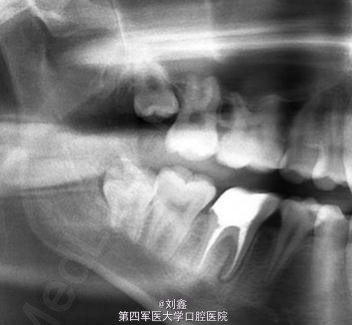

男,16岁,46因牙龈息肉就诊。

46牙牙龈息肉

局麻下牙龈息肉切除及开髓去腐,后牙根管治疗后纤维桩+树脂充填